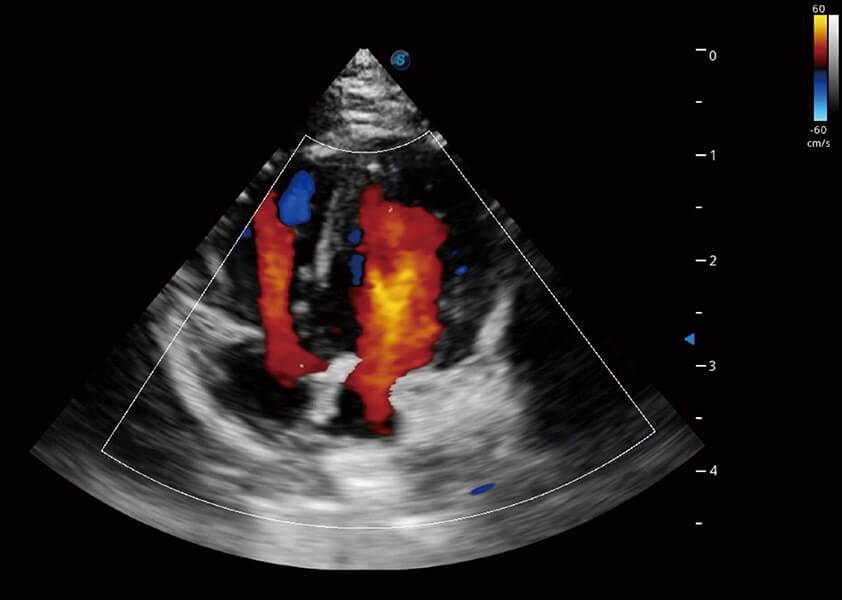

ProPet 60 作为一款高端台式动物超声设备,为动物医生的日常诊断提供了一系列贴合动物临床需求、解决临床实际问题的高级成像功能。凭借全系列高清探头,满足医生对腹部、心脏、生殖、浅表、肌骨等成像的所有需求,切实帮助您提升检查效率,提高诊断信心。

兽用彩色多普勒超声诊断系统

动物是人类最亲密的朋友和最值得信赖的伙伴。1xBET也一直致力于探索动物专用的超声影像解决方案。 全新推出的ProPet系列,是1xBET在动物超声影像智能化、专业化、精准化的一次跨越式革新。动物不能用言语来表述自己的不适,通过超声影像,ProPet系列搭建了动物医生与不同物种沟通的“桥梁”,为动物医生注入了“治愈之力”。